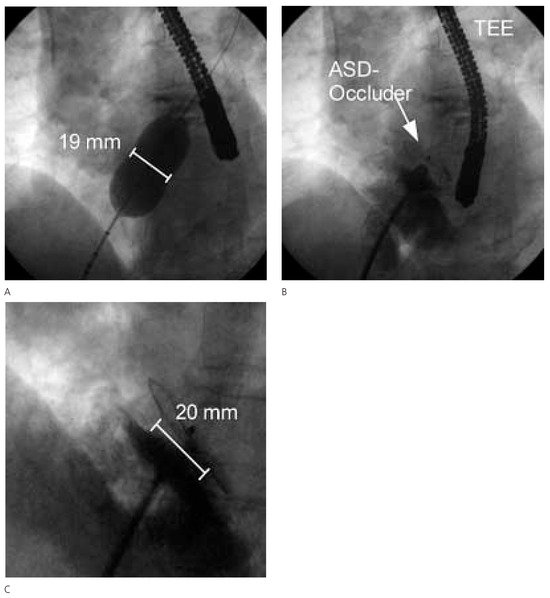

Platypnoe—Orthodeoxie: Eine Seltene Ursache Einer Lageabhängigen Dyspnoe und Arteriellen Hypoxämie

by Urs N. Dürst, Manfred Ritter, Beat Walder and Franz R. Eberli

Cardiovasc. Med. 2005, 8(10), 370; https://doi.org/10.4414/cvm.2005.01130 - 28 Oct 2005

Platypnea—orthodeoxia: a rare cause of positional dyspnea and arterial hypoxaemia. We report a case of an 83-year-old female patient, that developed positional dyspnea after a fall complicated by a thoracic spine compression fracture. In upright position the dyspnea was disabling occurring already with [...] Read more.

Platypnea—orthodeoxia: a rare cause of positional dyspnea and arterial hypoxaemia. We report a case of an 83-year-old female patient, that developed positional dyspnea after a fall complicated by a thoracic spine compression fracture. In upright position the dyspnea was disabling occurring already with normal daily activities, such as dressing. The dyspnea could be relieved by recumbancy. In supine position the patient’s arterial saturation was 94% and decreased to 86% in upright position. Transoesophageal echocardiography revealed an atrial septal defect with bi-directional shunt. The atrial septal defect was closed percutaneously with an Amplatzer-Septal-Occluder® 20 mm. Following the occlusion of the atrial septal defect, arterial oxygen saturation remained stable and the positional dyspnea disappeared. Full article